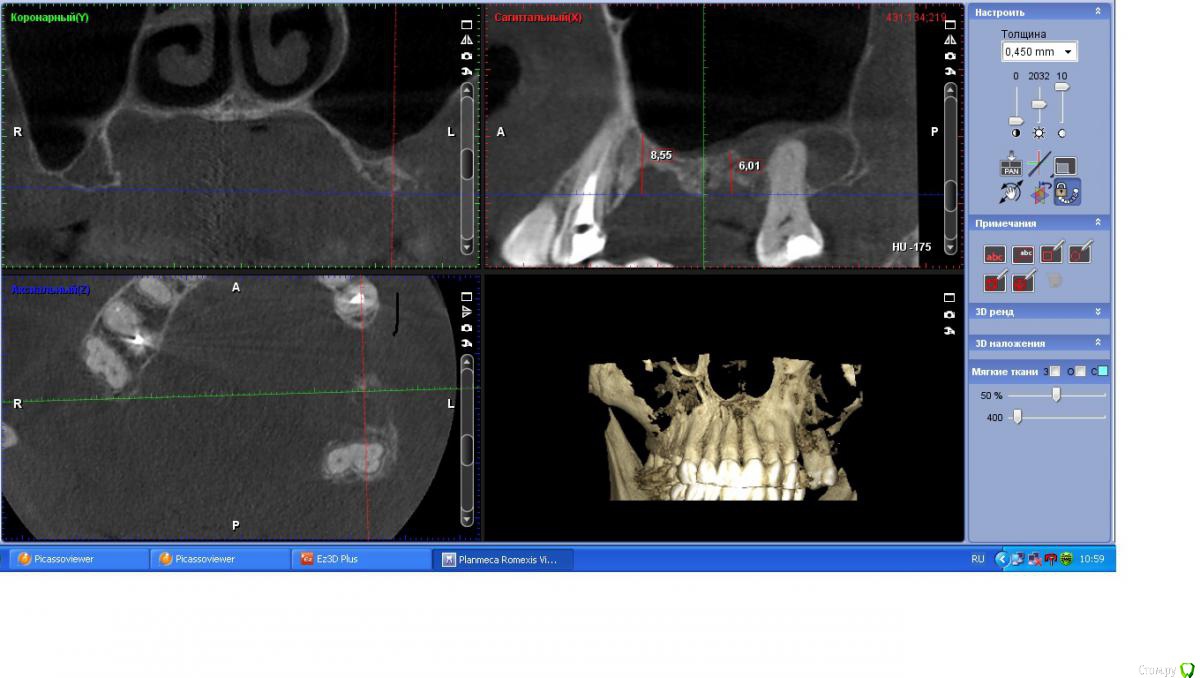

togrul Опубликовано 6 апреля, 2017 Поделиться Опубликовано 6 апреля, 2017 (изменено) Добрый день коллеги . Необходима Ваша помощь в планировании лечения. Пациентке нужно установить 2 имплантата в позиции 24-26. При анализе кт пришёл к выводу : 1 - провести НКР для восстановления высоты сеткой , через 6 месяцев установка имплантатов . 2- в области 27 зуба есть радикулярная киста , как вы считаете ее нужно убирать или нет и радикулярная ли данная киста? 3 - нужно ли проводить синус с нкр или лучше провести после НКР закрытый синус ? Буду благодарен за ответы.IMG_3292.BMPIMG_3293.BMPIMG_3294.BMP Изменено 6 апреля, 2017 пользователем togrul Ссылка на комментарий

Хью Крейн Опубликовано 6 апреля, 2017 Поделиться Опубликовано 6 апреля, 2017 Киста есть. Убирать лучше с зубом. Т.к. эндолечение вряд ли будет эффективно.Вестибулярно у зуба кости очень мало. Между кистой и верхнечелюстным синусом костная стенка есть. Синус лучше открытый,вместе с НКР. И ждать от 6 месяцев.Я бы сделал так. Ссылка на комментарий

togrul Опубликовано 6 апреля, 2017 Автор Поделиться Опубликовано 6 апреля, 2017 Спасибо за комментарий. Просматривая кт зуб 27 не вовлечен в полость кисты. Я завтра скину срезы другии, Но слизистая шнайдеровой мембраны сращена на мой взгляд с кистой . И еще один момент это рубец на границе неподвижной слизистой к подвижной. Ссылка на комментарий

togrul Опубликовано 29 августа, 2017 Автор Поделиться Опубликовано 29 августа, 2017 (изменено) Убрал содержимое кисты , получил мутное содержимое +убрал эпителий . Было сообщение полости с синусом . Ждал 3 месяца . Вот результат. Изменено 29 августа, 2017 пользователем togrul Ссылка на комментарий